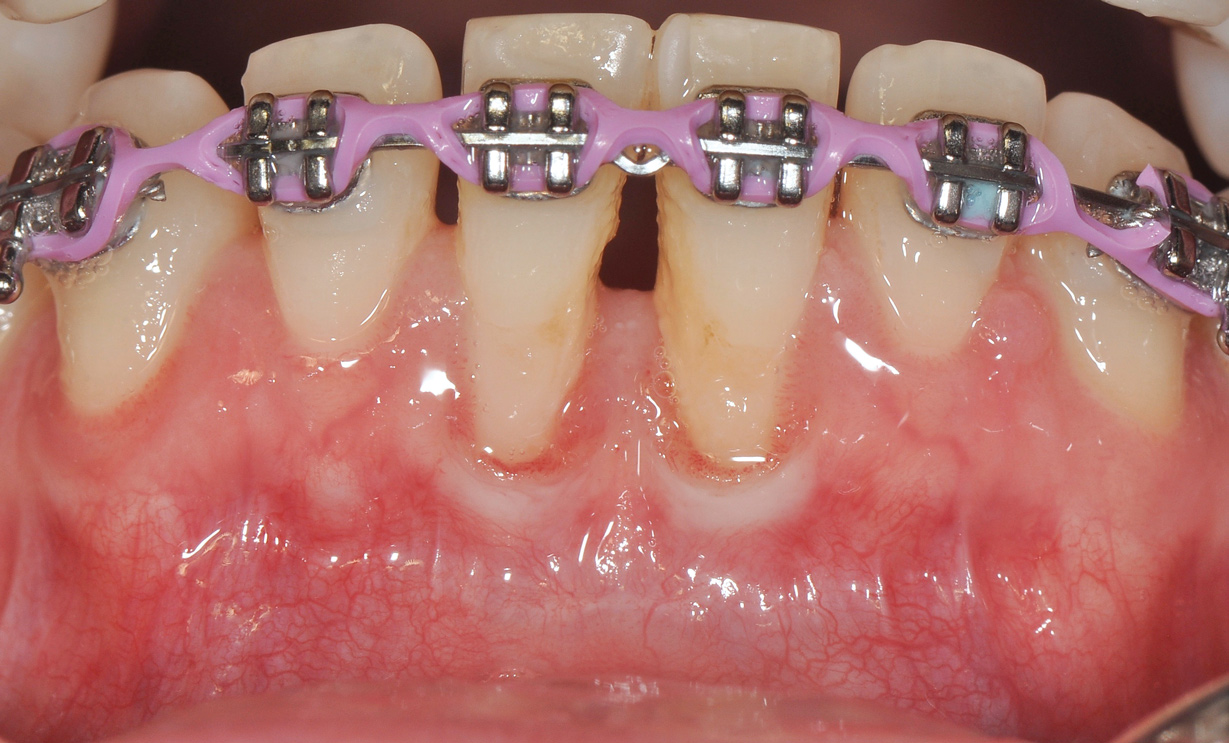

Although similar to the root coverage procedures mentioned above, gingival augmentation procedures not aimed at achieving root coverage are performed to facilitate plaque control, improve patient comfort, and prevent future periodontal recession. They may be used in conjunction with restorative, orthodontic, or prosthetic dentistry. The consensus report from the AAP's workshop group on soft-tissue non-root coverage procedures concluded that a specific minimum amount of keratinized tissue is not needed to prevent attachment loss when optimal plaque control is present; however, if plaque control is suboptimal, a minimum of 2 mm of keratinized tissue is needed. 12 A standard procedure that is recognized to predictably gain keratinized tissue is the use of an autogenous gingival graft.12 Figure 5 through Figure 8 demonstrate the healing progression of a patient with poor oral hygiene whose mucogingival defect was treated with a free gingival graft and L-PRF from the patient's own blood.

(5.) Pretreatment photo of patient with recession to be treated with a free gingival graft (harvested from the palate) and L-PRF.

Figure 5

(7.) Postoperative view of the graft recipient site after 3 weeks showing healing progress with poor oral hygiene.

Figure 7

(8.) Postoperative view of the graft recipient site after 6 months showing healing progress with poor oral hygiene.

Figure 8